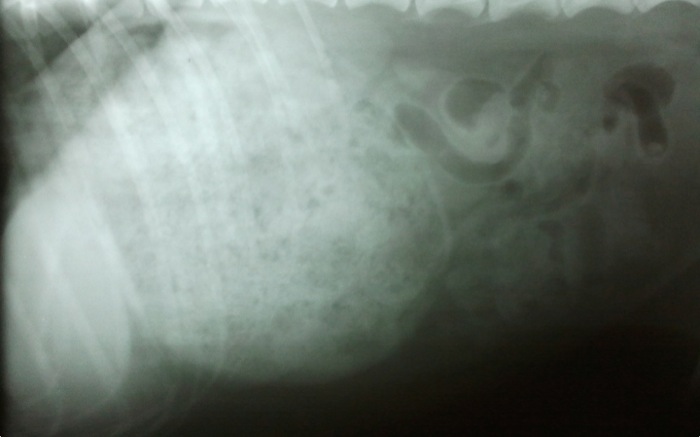

| Pruebas | Radiografía con contenido radiodenso en estómago como en la ingestión de tejidos. Al entrar en quirófano presenta taquicardia a 240 lpm y una presión arterial indetectable pero conseguimos antes de empezar la cirugía que aparezca en el monitor y mantener la sistólica en valores por encima de 77 durante toda la cirugía. |

La imagen con esta densidad y áreas radiolúcidas es habitual en ingestión de tejidos. Sólo se premedica con 0,05 ml de Equipromacina® (0,24 mg de acepromacina, 20% de lo habitual) y 0,35 de Metasedin® (3 mg de metadona, 25% de lo habitual). La taquicardia se empieza a normalizar más cuando se comienza con el vaciado de estómago. Propofol (3ml) e intubamos.